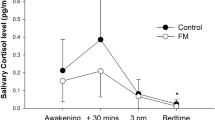

The HRV results by phase are shown in Table 1. The base GLS model (Outcome = Group × Time + Baseline) showed that the HRV variables responded to the stress-relaxation protocol with increased HR and decreased RRmean during both stress phases and the intermediary relaxation phase between them, and decreased RMSSD and SDNN during the stress phases. FM patients’ HR response to the second stress phase and RRmean response to the stress phases and the intermediary relaxation phase were lesser than in the controls (Table 2). These differences remained even after adjusting for BMI, smoking, and LTPA (Table 3).

Overall, we found FM patients to have higher heart rates and lower HRV, compared with healthy controls. The HRV stress responses were also attenuated in FM patients, compared with controls, and this attenuation was more pronounced with repetition of cognitive stress.